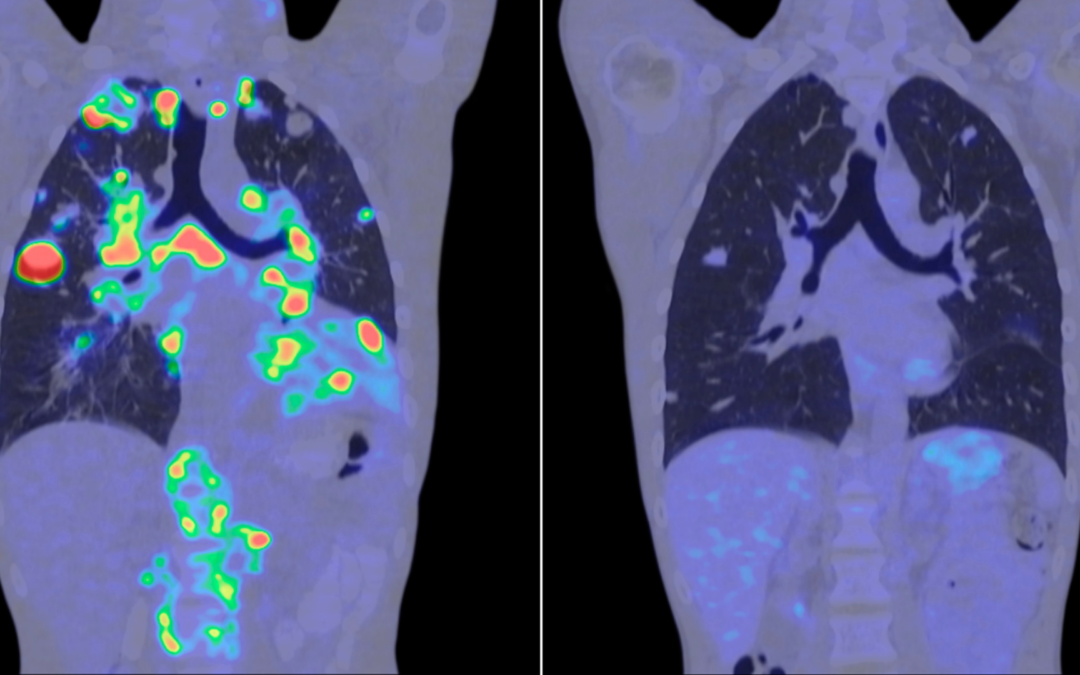

La inteligencia artificial abre una nueva etapa en la investigación contra el cáncer La inteligencia artificial ha dejado de ser una promesa futura para convertirse en una herramienta real dentro del ámbito sanitario. En los últimos meses, distintos estudios han...